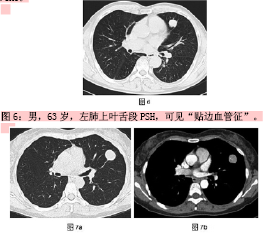

肺硬化性血管瘤的MSCT诊断分析